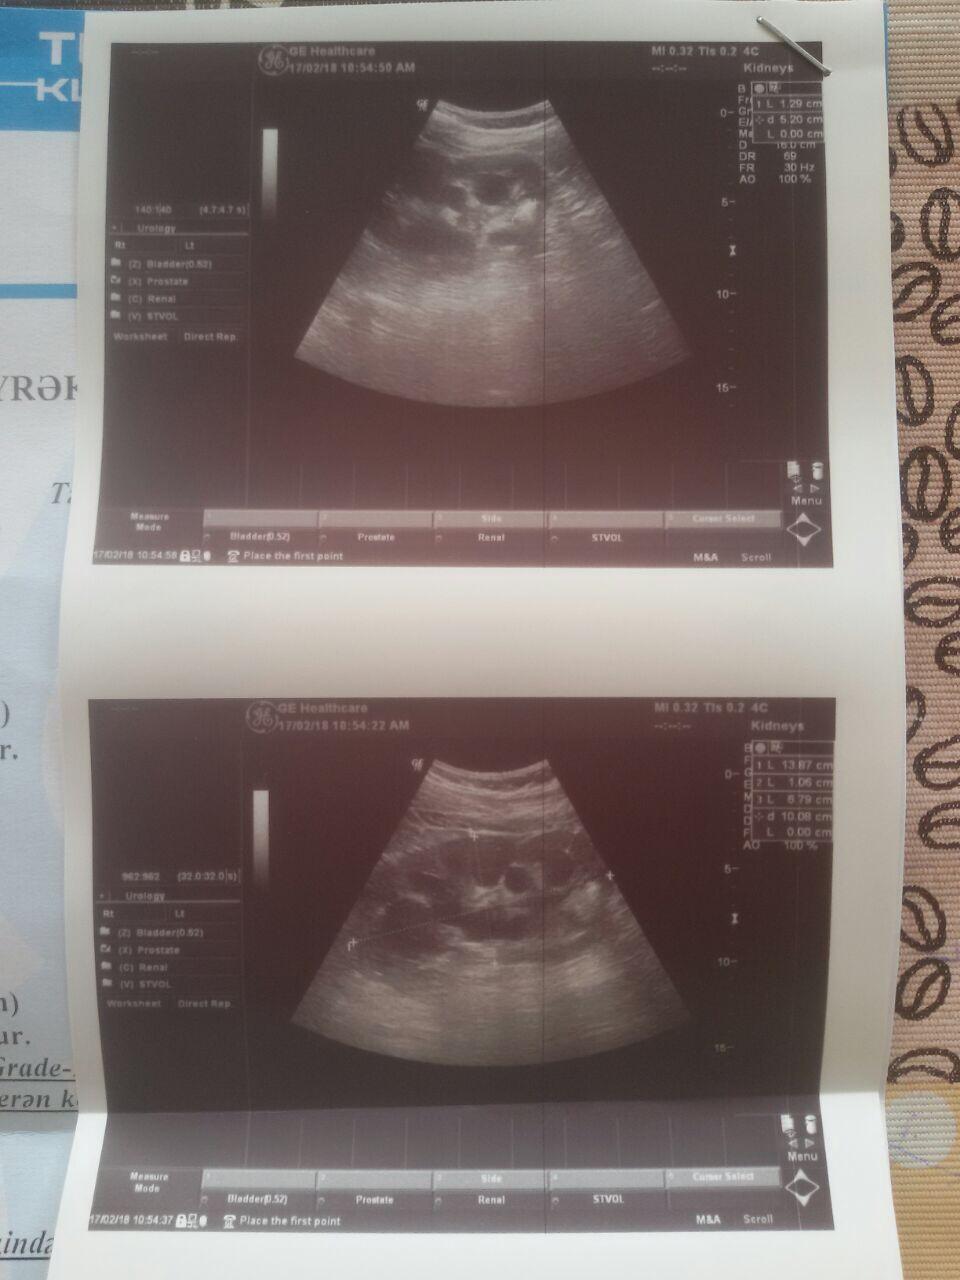

Второй вопрос. У брата та же проблема с левой почкой. Операцию делали лет 10 назад. Без стенда с катетрами и дренажами. Сейчас ему диагностируют гидронефроз 3 степени с камнями. Фото УЗИ прилагается Лечащий врач поставил стент. Сказал раздробим и выведем камни а дальше видно будет. Про удаление даже не заикается. Говорит все будет хорошо. Возможна повторная операция для расширения прохода. Хотел бы узнать ваше мнение по обоим вопросам. Тоесть нормально ли то что операция у меня вроде успешная а гидронефроз не совсем изчез. И можноли еще что то сделать с третей степенью гидронефроза у брата или это скорее всего потеря органа. ( анализы в порядке у него. Белка и креатинина нет, а вот давление иногда мучает).